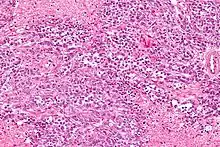

Micrograph of a mucinous ovarian carcinoma stained by H&E

Mucinous adenocarcinoma

Mucinous adenocarcinomas make up 5–10% of epithelial ovarian cancers. Histologically, they are similar to intestinal or cervical adenocarcinomas and are often actually metastases of appendiceal or colon cancers. Advanced mucinous adenocarcinomas have a poor prognosis, generally worse than serous tumors, and are often resistant to platinum chemotherapy, though they are rare.[29]